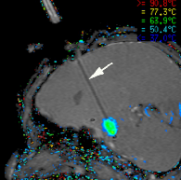

LITT激光间质热疗:针对医学难治性癫痫,目前各种手术技术都在突飞猛进。不同于传统的开颅手术,药物难治性癫痫的手术选择又有了新的“微创”之选—...

坚持合理用药却收效甚微,药物难治性癫痫患者要做开颅手术吗?不妨听听神界神外教授Rutka教授如何利用LITT技术治疗癫痫...